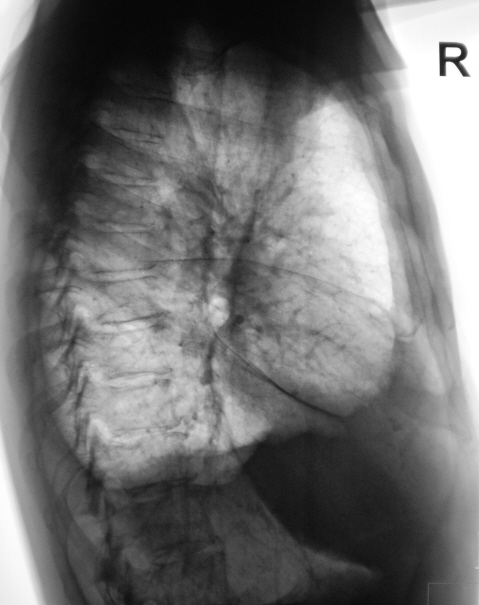

При расшифровке флюорограмм пациент взят на контроль. При общении с пациентов выяснено, что месяц тому от упал на правый бок. В настоящее время боли справа есть, вечером имеет место повышение температуры. Произведена рентгенография в прямой и правой боковой проекциях, выявлен выпот справа, обнаружены переломы ребер по подмышечной линии. С учетом теневой картины на правой боковой рентгенограмме произведена томография в боковой проекции.

Ситуация обычная. Постравматические изменения в виде частично-консолидированных переломов боковых отрезков ребер справа, организующийся гемоторакс, с посдедующим осумкованием и исходом в фиброторакс.

Гематоракс в стадии организации.

Учитывая месячной давности травму и переломы ребер, можно говорить что изначально, скорее всего, был гематоракс. И на данный момент гематоракс организуется, а при лизисе гематомы возможен подъем температуры, обусловленный продуктами распада. Смущает отсутствие клиники в первые дни после травмы (или надо уточнить у пациента). Возможно также вторичное инфицирование и развитие пиоторакса, кровь как никак хорошая среда. Если честно, на мой взгляд, в данной ситуации для оценки характера выпота показано проведение УЗИ. Наши специалисты очень хорошо на УЗИ видят и выпот и взвесь и фибриноторакс, что без пункции, в большинстве случаев, помогает определится с диагнозом и назначить терапию.